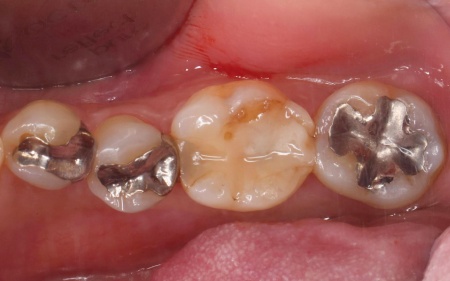

治療前

治療中

治療後

| 診断 | 拝見したところ、左下奥歯にプラスチックの詰め物であるコンポジットレジンが詰められていましたが、隣り合う歯との間が欠けている状態でした。

このまま放置すると、欠けた隙間から細菌が入り込んで虫歯が再発するおそれがあります。 |

| 行ったご提案・治療内容 | 患者様は「審美性が高く、丈夫な素材で修復したい」と希望されています。 そこで、新しい詰め物の形状はより強度を高めるため、噛む力を覆うように広範囲を修復する「アンレー」を用いることを提案し、同意いただきました。 また、詰め物の素材には「セラミック」の一種である「E-MAX(イーマックス)」を採用しています。 E-MAXのメリット E-MAXのデメリット まずは古いコンポジットレジンを除去し、アンレーを装着するために歯の形を整えます。 その後、型取りを行い、仮詰めをして初回の治療を終了しています。 後日、完成したE-MAXアンレーを装着し、歯にぴったりと合っているか、噛み合わせに問題がないかを確認して、治療を終了しました。 |